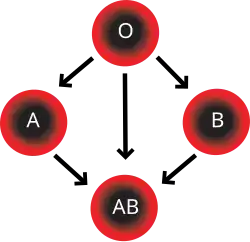

- Blood group AB individuals have both A and B antigens on the surface of their RBCs, and their blood plasma does not contain any antibodies against either A or B antigen. Therefore, an individual with type AB blood can receive blood from any group (with AB being preferable), but cannot donate blood to any group other than AB. They are known as universal recipients.

- Blood group A individuals have the A antigen on the surface of their RBCs, and blood serum containing IgM antibodies against the B antigen. Therefore, a group A individual can receive blood only from individuals of groups A or O (with A being preferable), and can donate blood to individuals with type A or AB.

- Blood group B individuals have the B antigen on the surface of their RBCs, and blood serum containing IgM antibodies against the A antigen. Therefore, a group B individual can receive blood only from individuals of groups B or O (with B being preferable), and can donate blood to individuals with type B or AB.

- Blood group O individuals have no A or B antigens on the surface of their RBCs, and their blood serum contains IgM anti-A and anti-B antibodies. Therefore, a group O individual can receive blood only from a group O individual, but can donate blood to individuals of any ABO blood group (i.e., A, B, O or AB). If a patient needs an urgent blood transfusion, and if the time taken to process the recipient's blood would cause a detrimental delay, O-negative blood can be used. Because it is compatible with anyone, there are some concerns that O-negative blood is often overused and consequently is always in short supply.[33] According to the Association for the Advancement of Blood and Biotherapies (AABB) and the British Chief Medical Officer's National Blood Transfusion Committee, the use of group O RhD negative red cells should be restricted to persons with O negative blood, women who might be pregnant, and emergency cases in which blood-group testing is genuinely impracticable.[33]

In addition to donating to the same blood group, type O blood donors can give to A, B, and AB; blood donors of types A and B can give to AB.